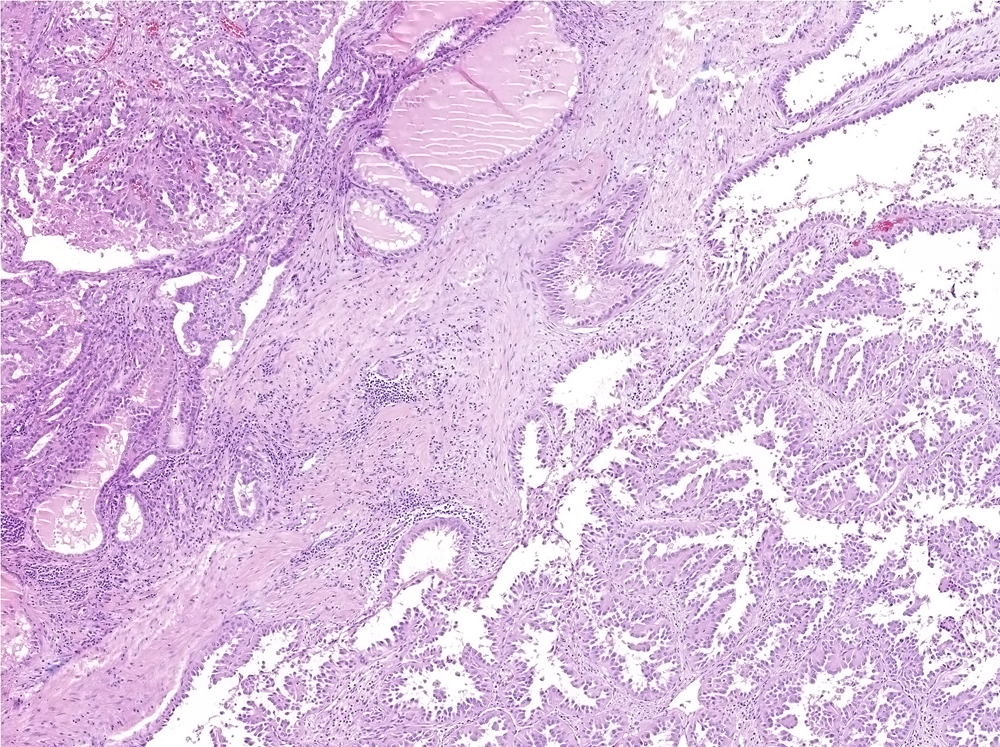

Renal tumor grading

Case ID: 488